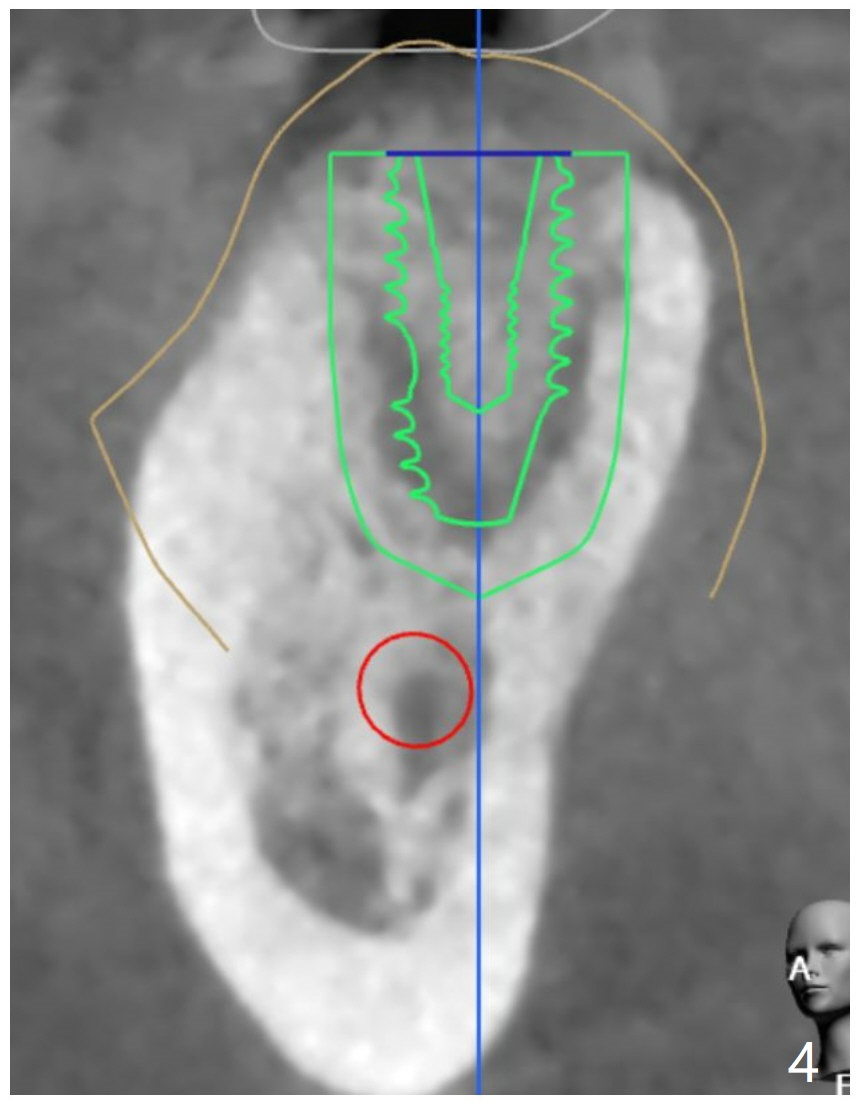

Seven months post socket preservation. Due to coronavirus, the surgery is postponed for 3 months. When the patient returns, take a PA for density check using sensor I. Also take a PA for #3 implant. Take 5x5 pre- (crestal cortex formation? (10 months post socket preservation)) and post-op.